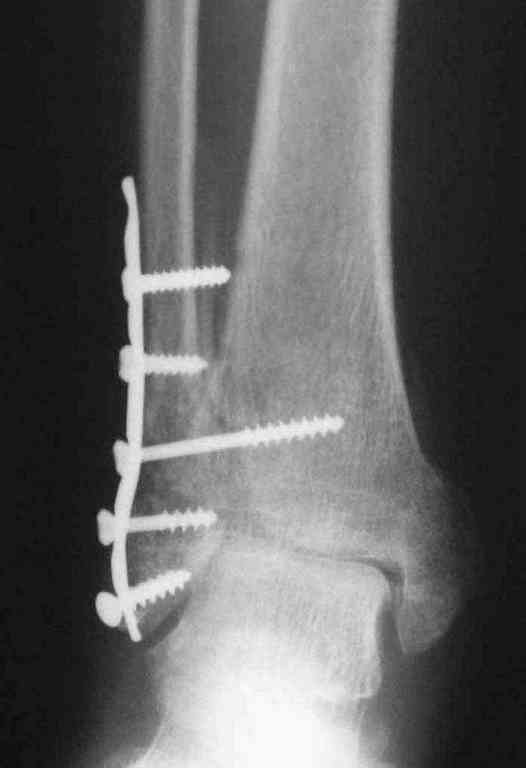

Уже 15 лет в отделении мы активно оперируем свежие переломы ГСС по принципам АО и вполне удовлетворены результатами лечения свежей травмы. В случаях же операций при позднем поступлении или реконструкции после неудачных вмешательств в ряде случаев сохраняется нестабильность ГСС, тенденция к вальгусной деформации. В свежих случаях никогда не приходилось производить шов дельтовидной связки, пластики тоже ни разу не выполнялись. Два примера на снимках.Первый - врач 38 лет, неудачно оперированный в своей больнице с двухлодыжечным переломом, разрывом МБС был повторно оперирован через 8 месяцев. Пытались восстановить длину наружной лодыжки остеотомией, освежили МБС, два месяца функционального лечения без нагрузки на стопу.Сейчас ходит с легкой хромотой, устает к обеду, вальгусное отклонение стопы корригировано супинатором. На Рграммах видны дистрофические изменения латерального эпифиза большеберцовой кости. Первый снимок через 6 месяцев после травмы, операции остеосинтеза болтом-стяжкой, удаленной по причине нестабильности и наличия свища над металлом. Второй снимок через 3 месяца после реконструктивной операции.

По снимкам в первом случае, укорочение малоберцовой приблизительно около 8-10 мм. Удовлетворительным восстановлением длины малоберцовой считается, когда на снимке суставная щель равны со всех сторон.

Несмотря на прошедшее время с момента травмы и попытки восстановления, мы бы рекомендовали повторить процедуру по сохранению сустава. Для этого очищается синдесмоз от фиброза, удлиняется малоберцовая на мортизной ренгенограмме засчет проксимальной поперечной остеотомии вставлением расширящего инструмента (lamina spreader).